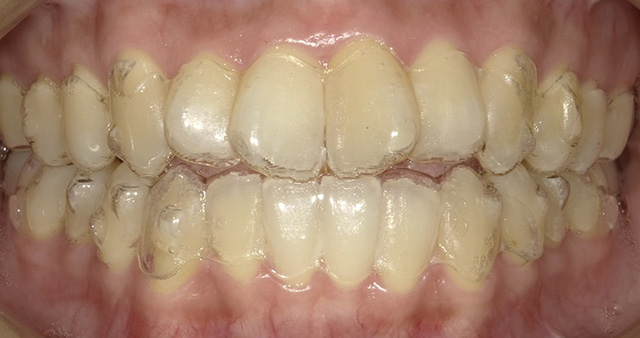

マウスピース型の矯正器具を装着して歯を動かす治療です。マウスピースは透明の医療用のプラスチック製で、目立たず、周囲に気づかれずに治療が受けられるという特徴があります。取り外しが可能で、いつも通りに食事や歯みがきをすることができます。